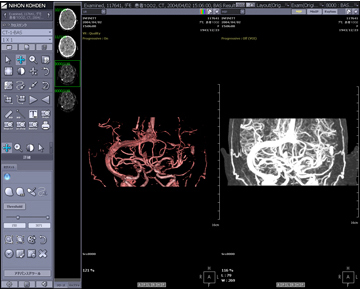

Dioramの最大の特徴は,PACS,3D作成機能(VR,MIP,MPR,仮想内視鏡),レポート機能,さらに心電図・動画ファイリングも含めて1つのシステムで構築可能な点にあります(図1)。1つのシステムで構築するメリットとしては,初期導入費用および保守費用などのコスト削減が挙げられます。また,2Dと3D表示が相互にリンクして表示される点もメリットの1つです(図2)。例えば,3Dで表示された病変部にポインタをマークすると,3D画像にリンクしてaxial断面像,coronal断面像,sagittal断面像それぞれにポインタが表示されるため,インフォームド・コンセントなどに利用可能です。さらに放射線科領域の検査データだけでなく,心電図波形,エコー動画,内視鏡画像やデジタルカメラで撮影した病理画像などの汎用画像ファイル(JPEG,BMP,TIFF)もファイリングすることで,部門システムにとどまらない院内のIT化を実現します。

![]() 図2 2Dと3Dのリンク表示 大きく表示されたVR画像と,画面右側に表示されたaxial, coronal, sagittalの各断面像はマウスクリックで相互にリンクしてカーソルが表示されます。 |